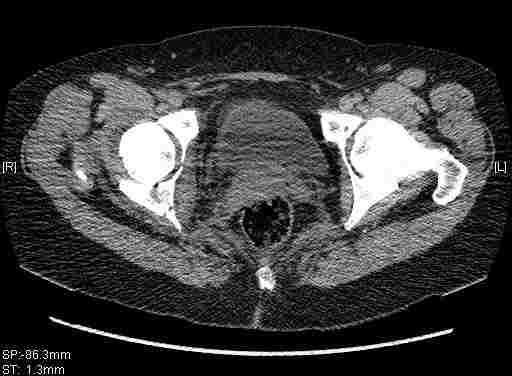

Re: Т-образный перелом вертлужной впадины

Удалось сегодня вывести пациентку в соседнюю больницу, где есть кт. Срезы сделаны только горизонтальные.